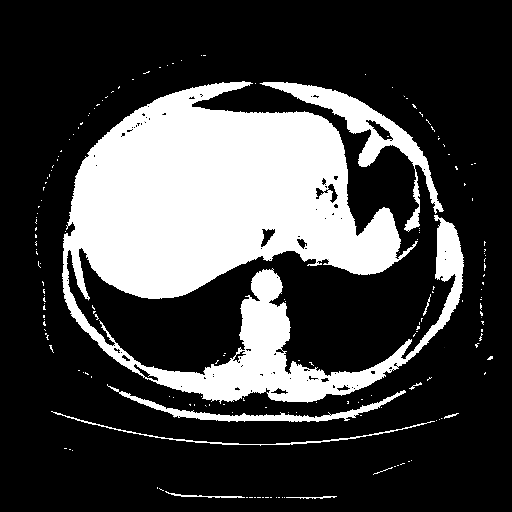

Original VENOUS CT scan

Full window (WL 1023.5, WW 4095 β†’ Low βˆ’1024, High +3071)

Actual HU range: [-1024.0, 3071.0]